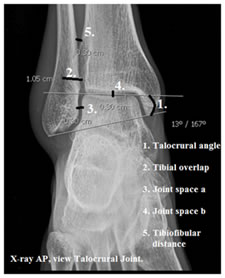

To study the normal X-Rays and try to measure normal parameters so as to be useful in diagnosing the ligament tears when there are no fractures evident on X-Rays in the west coast population.

This study was done in the Department of Anatomy, Srinivasa Medical College, Mangalore. This study was done from March 2014 to February 2016. One hundred X-Rays were collected from the Department of Radiology and the study was done. The following were measured.

It is important to use whatever is available and try to come to a diagnosis and that’s where the study of the basic sciences comes in handy. Use of the basic knowledge to come to definitive diagnosis is what is meant to be a good doctor instead of heavily relying on the advances in the field of sciences. Patil MS et al.10 in 2012 in their study on anthropometric measurements of ankle mortise for evaluating mortise fracture reductions with an aim to develop contoured implants measured the talocrural angle, tibiofibular clear space, tibiofibular overlap and compared joint clear space at two places. Anteroposterior radiographs, of both ankles in 20 adult individuals formed the material. They agreed that the talocrural angle of two ankles of a given individual does not vary by more than 2 degrees. Tibiofibular clear space on Anteroposterior radiographs measured a mean value of 2.4 mm with a standard deviation of 1.3 mm. Tibiofibular overlap on Anteroposterior radiographs was measured as 11.2 mm with a standard deviation of 4.4 mm. Joint spaces at two levels were almost equal. Chen Yan-Xi et al.11 in 2011 on a study of three-dimensional morphological characteristics measurement of ankle joint based on computed tomography image post-processing, commented that the mean talocrural angle (10.01±0.38)° was measured to be 10.1 degrees with a standard deviation of 0.38 degrees Tibiofibular clear space mean measurements were 2.78 mm, with a standard deviation of 0.19 mm. There was no significant correlation to gender, height and weight (P >0.05) in 100 cases, (50 males and 50 females). This study helps to firmly put in a foundation towards forming measurement standards so as to be helpful in diagnosing the ligament injuries.